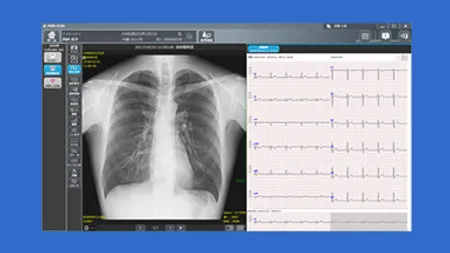

日本光電工業株式会社

PrimePartnerで利用できる医療機器プログラムです。医用画像診断装置で撮影された画像の表示、計測と、心電図の導出18誘導を演算表示します。